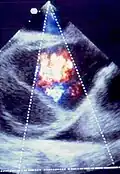

| Transösophageale Echokardiografie (TEE) |

TEE mit Farbdoppler farbig wahres Lumen |

| Querschnitt durch die Aorta ascendens 1 Dissektionsmembran – 2 Aortenklappe | |

Bei der üblichen Ultraschalluntersuchung des Bauchraumes (abdominelle Sonografie) können die im Bauchraum gelegenen Abschnitte der Aorta (Aorta abdominalis) meist dargestellt und mehr oder weniger gut beurteilt werden. Zusätzlich sind im Rahmen der normalen Ultraschalluntersuchung des Herzens (Echokardiografie) oft die ersten zwei bis fünf Zentimeter der Aorta mäßig gut beurteilbar. Insgesamt ist aber die diagnostische Genauigkeit der einfachen Ultraschallverfahren zur Erkennung von Aortenerkrankungen nur mäßig, weil die Darstellungsqualität durch die Brust- und Bauchwand hindurch oft schlecht ist und Teile der Aorta ascendens sowie der Aortenbogen und die im Brustraum gelegenen Abschnitte der Aorta descendens nicht beurteilbar sind (Sensitivität 59–85 %, Spezifität 63–96 %).

Die TEE hingegen erlaubt eine gute Darstellung der herznahen Aortenabschnitte und der Aorta descendens im Brustraum. Aufgrund der hohen räumlichen Auflösung ist eine vorhandene Dissektionsmembran fast immer zu erkennen, mit Hilfe der Dopplertechnik kann darüber hinaus das wahre Lumen zuverlässig vom falschen Lumen abgegrenzt werden. In vielen Fällen sind das entry und ein evtl. vorhandenes re-entry sichtbar. Eine Aortenklappeninsuffizienz kann ebenso exakt diagnostiziert werden wie ein Perikarderguss. Hingegen sind Veränderungen am Aortenbogen, an den dort entspringenden hirnversorgenden Gefäßen und an der Aorta abdominalis in der TEE oft unzureichend dargestellt, diese Regionen werden auch als „blinde Flecken“ der TEE bezeichnet. Die Sensitivität zur Erkennung von Aortenerkrankungen beträgt 88–99 %, die Spezifität 95–98 %.